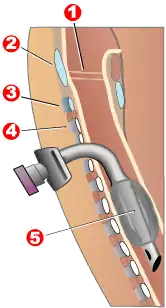

Completed tracheotomy: 1 – Vocal folds | |

Components

A tracheostomy tube may be single or dual lumen, and also cuffed or uncuffed. A dual lumen tracheostomy tube consists of an outer cannula or main shaft, an inner cannula, and an obturator. The obturator is used when inserting the tracheostomy tube to guide the placement of the outer cannula and is removed once the outer cannula is in place. The outer cannula remains in place but, because of the buildup of secretions, there is an inner cannula that may be removed for cleaning after use or it may be replaced. Single-lumen tracheostomy tubes do not have a removable inner cannula, suitable for narrower airways. Cuffed tracheostomy tubes have inflatable balloons at the end of the tube to secure them in place. A tracheostomy tube may be fenestrated with one or several holes to let air through the larynx, allowing speech.[8]

Special tracheostomy tube valves (such as the Passy-Muir valve[9]) have been created to assist people in their speech. The patient can inhale through the unidirectional tube. Upon expiration, pressure causes the valve to close, redirecting air around the tube, past the vocal folds, producing sound.[10]